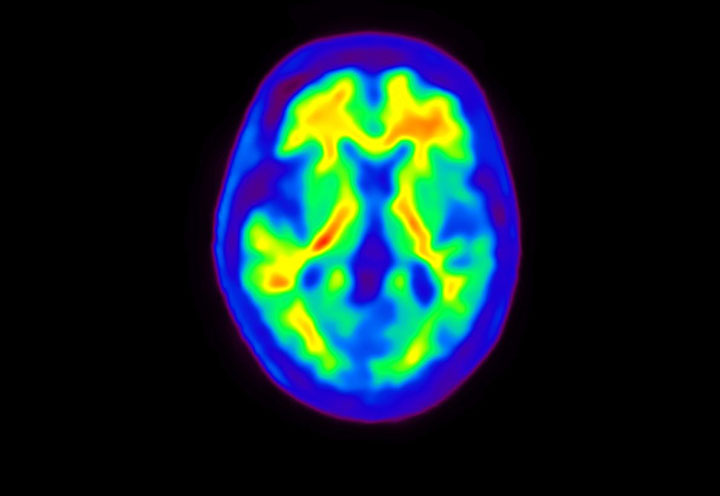

Head / Case4 : Amyloid

Axial

Courtesy : Kindai University Hospital

- Imaging protocol

- Injected dose: 3.21 MBq/kg, 18F-Flutemetamol

- Uptake time: 100 minutes

- Scan time: 20 minutes